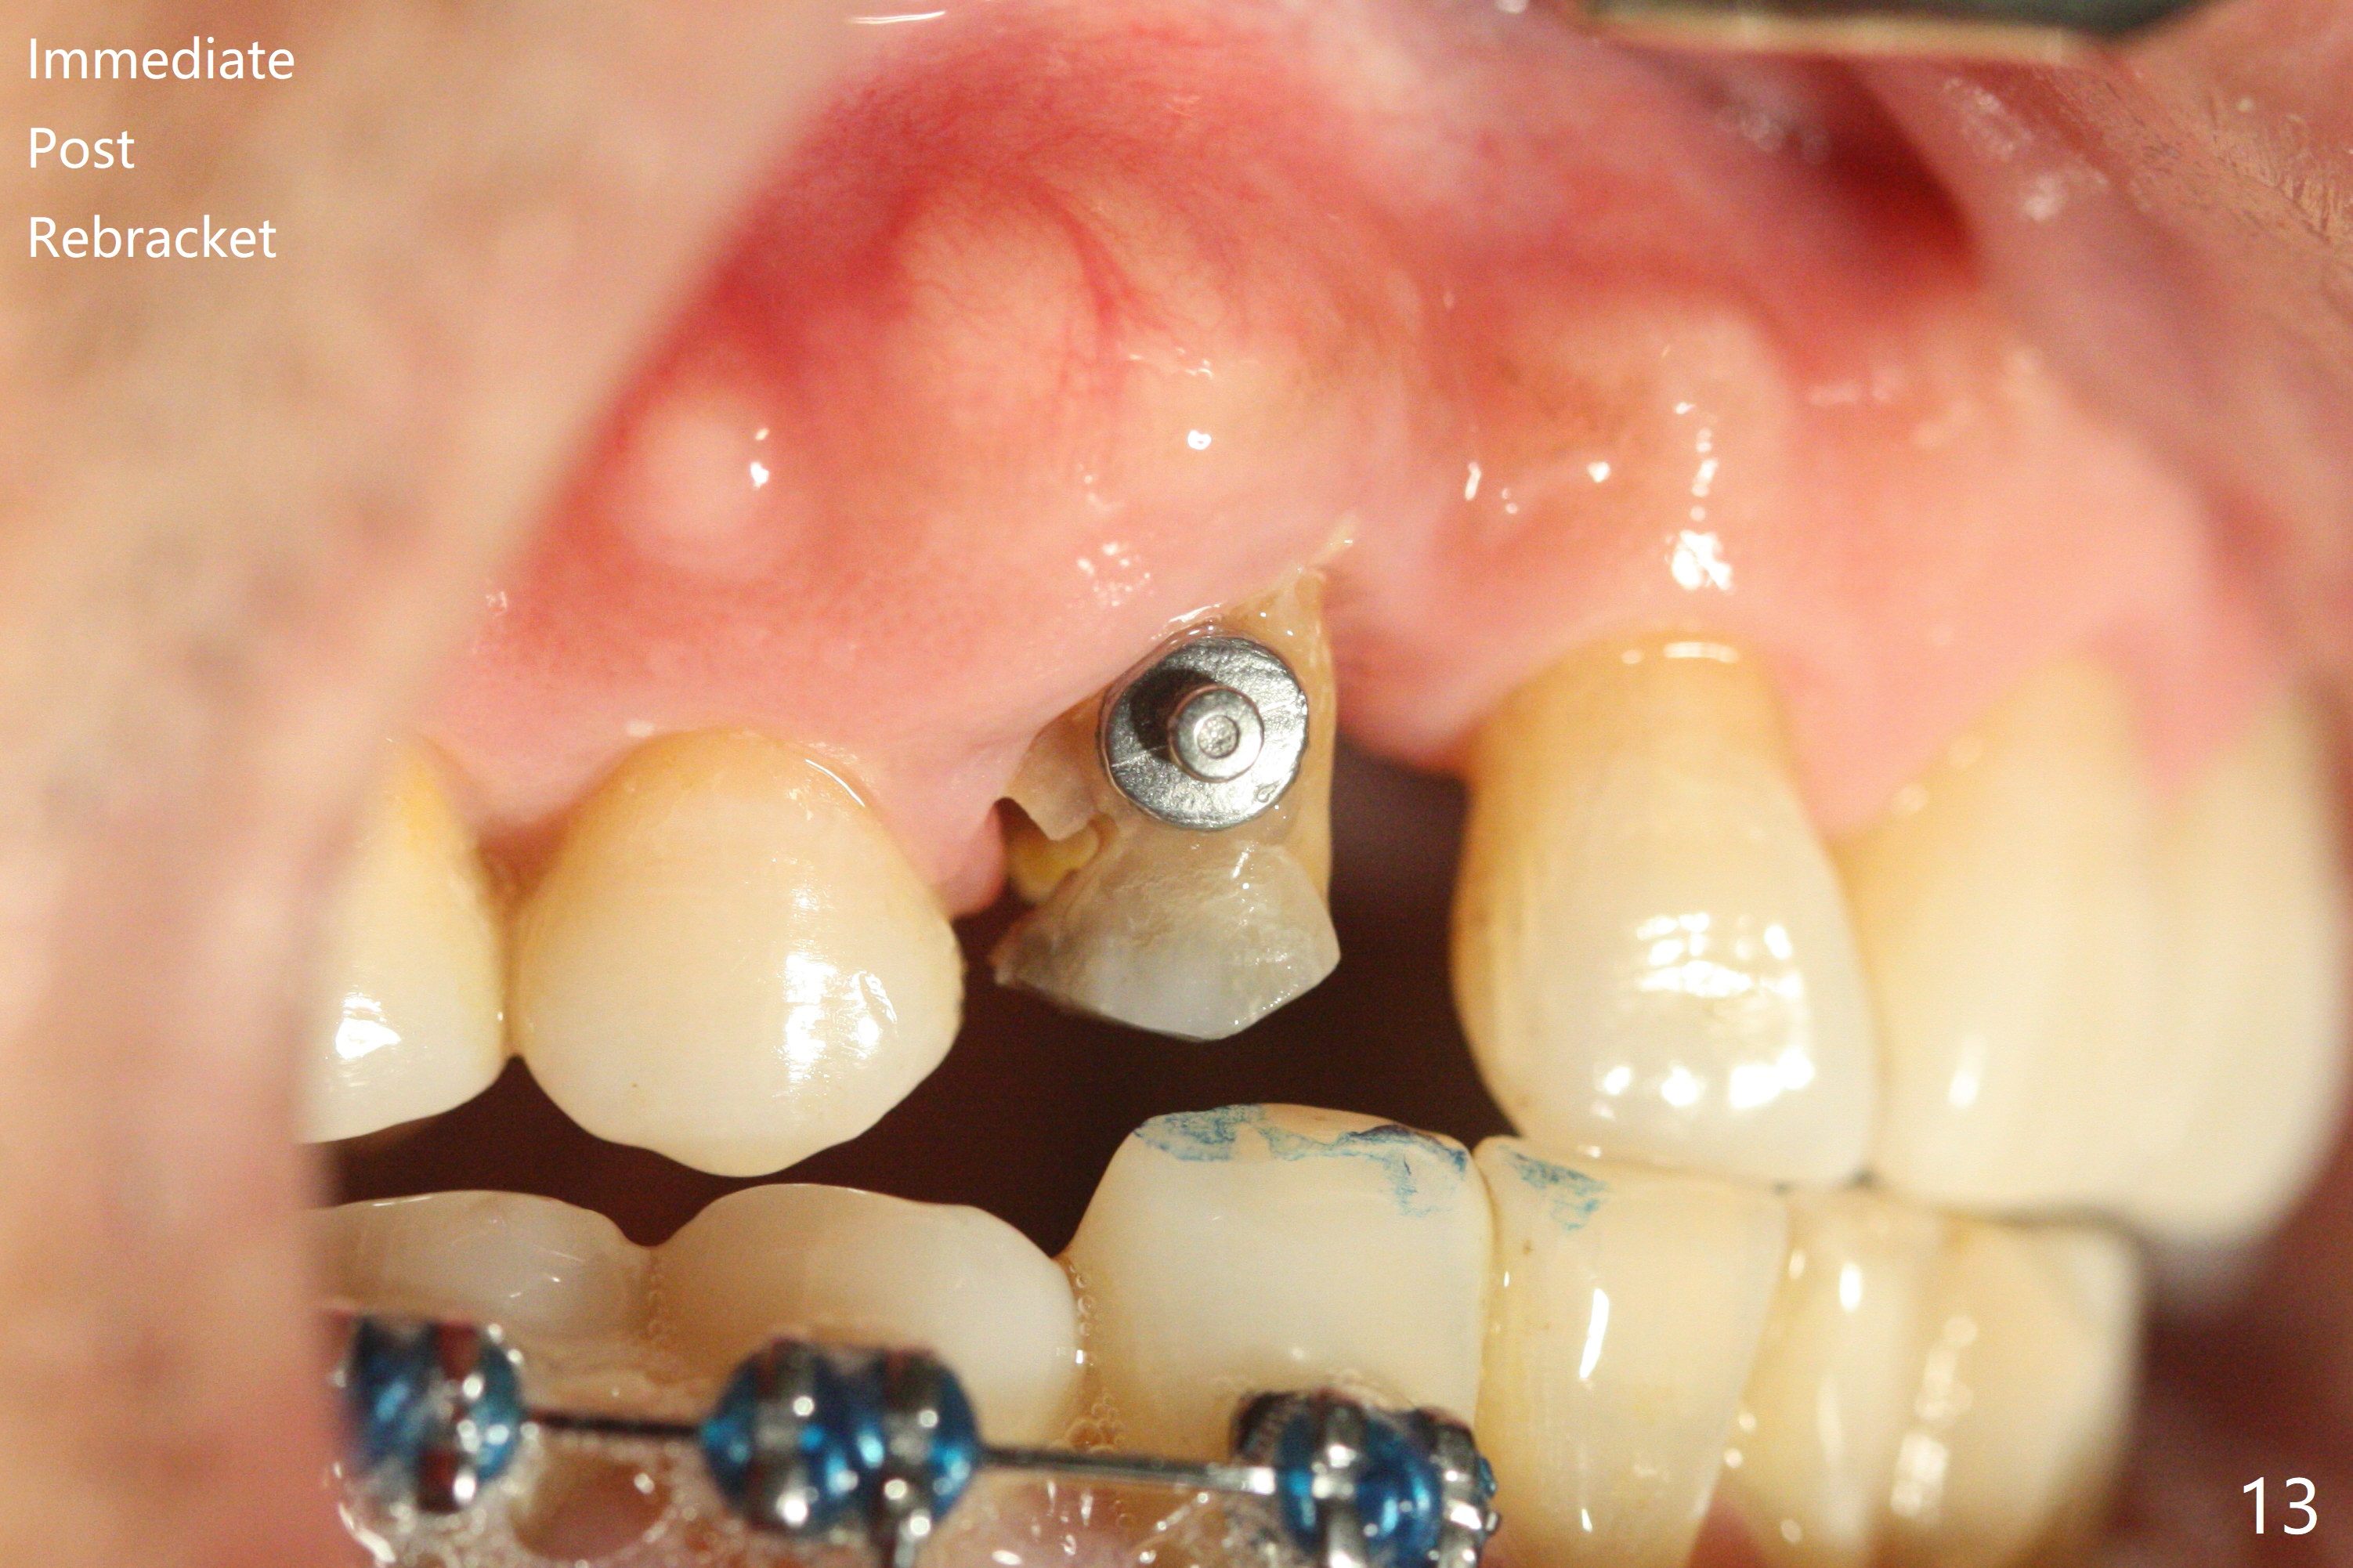

A 62-year-old man had traumatic root fracture at #6 in his teen. The tooth remained asymptomatic until his fifties. Following root canal therapy (Fig.1), the tooth is orthodontically extruded (~ 5 years, Fig.2 (*: bracket)) with apparent disappearance of the infection. The bone distal to #7 seems to increase in height (Fig.3, as compared to Fig.1) and in density (Fig.4). Bone graft could be placed for regeneration with PRF or GEM21S (Fig.5 red (between #6 and 7), pink (buccal to #7 or coronal to the fracture line) circles). With extrusion, the oblique fracture line is more than half or two third supragingival (Fig.6). In spite of severe bone loss, exostosis is present (Fig.7 (mesiobuccal view) E) so that bone graft could be placed palatal to it (Fig.8 red). In case the tooth is non-salvageable, immediate implant will be placed with guide (Fig.9,10). Move lingual button as apical as possible (Fig.12) and make occlusal clearance. Continue extrusion until all of the crack is exposed without deep pocket.